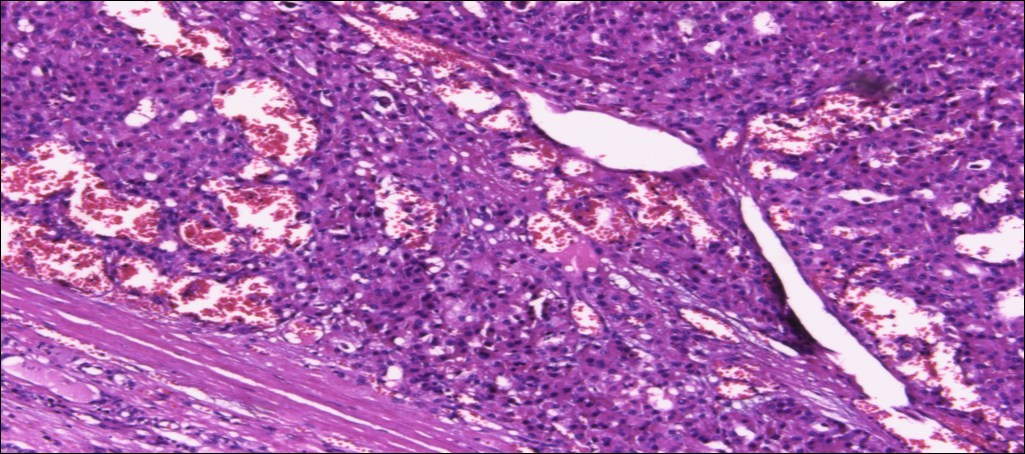

甲状腺嗜酸性细胞腺瘤

(甲状腺右叶及峡部):暗褐结节,直径6cm,包膜完整

肿物包膜完整,镜下未见明确包膜、脉管侵犯

镜下可见包膜,脉管侵犯!

YT***:

好,收到,谢谢老师,我还以为不是呢